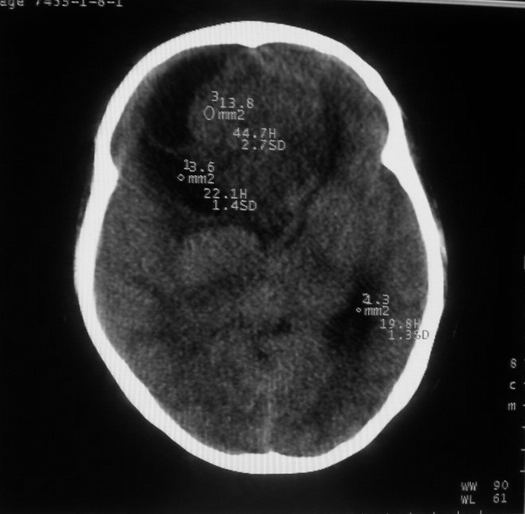

女,44岁,头痛数月。

右侧额叶占位性病变,考虑脑肿瘤;建议行进一步检查。

右侧额叶占位性病变,考虑脑膜瘤可能性大;建议行进一步检查。

考虑为额叶占位;肿瘤可能?建议行进一步检查。